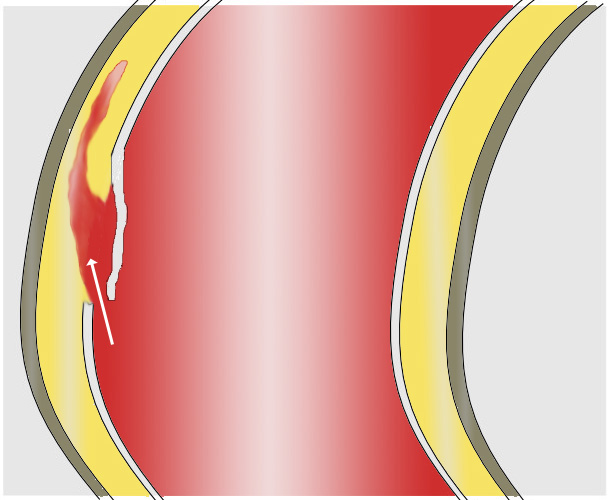

대동맥은 모든 동맥과 마찬가지로 내막, 중막, 외막의 세 층으로 구성되어 있다. 내막은 혈관 내부의 혈액과 직접 접촉하며, 주로 내피 세포 층으로 구성되고 그 아래에는 기저막이 존재한다. 중막은 결합 조직과 근육 조직을 포함하며, 혈관은 결합 조직으로 구성된 외막에 의해 외부에서 보호된다.

대동맥 박리에서 혈액은 내막을 관통하여 중막으로 들어간다. 높은 압력으로 인해 중막의 생물학적 조직이 찢어지며, 중막의 안쪽 2/3과 바깥쪽 1/3이 층상으로 분리된다.[22] 이 현상은 대동맥의 길이를 따라 앞쪽 또는 뒤쪽으로 다양하게 진행될 수 있다. 혈류 방향으로 진행되는 박리는 전방성 박리, 혈류 반대 방향으로 진행되는 박리는 역행성 박리라고 한다. 초기 파열은 보통 대동맥판막에서 100mm 이내에서 발생하므로, 역행성 박리는 쉽게 심낭을 손상시켜 혈액심낭증을 유발할 수 있다. 전방성 박리는 대동맥의 장골 분기점까지 진행되거나, 대동맥 벽을 파열시키거나, 혈관 내강으로 재관통하여 이중 내강 대동맥을 형성할 수 있는데, 이는 혈류의 압력을 완화하고 파열 위험을 감소시킨다. 파열은 체강 내 출혈을 유발하며, 예후는 파열 부위에 따라 달라진다. 후복막 파열과 심낭 파열이 모두 가능하다.[23]

대동맥 박리는 대동맥 내막에 파열이 생기면서 시작된다. 대동맥의 높은 압력으로 인해 혈액이 파열 부위에서 중막으로 들어가고, 이 힘은 파열을 확대시킨다. 파열은 근위부(심장 가까이) 또는 원위부(심장 멀리) 또는 양쪽 모두로 확장될 수 있다. 혈액은 중막을 통과하면서 가성 동맥류를 생성한다(진성 내강은 대동맥 내 혈액의 정상적인 통로이다). 가성 내강과 진성 내강을 분리하는 것은 내막 조직층으로, 이를 내막 플랩이라고 한다.

대부분의 대동맥 박리는 상행 대동맥(65%), 대동맥궁(10%), 또는 동맥관 바로 원위부의 하행 대동맥(20%)에서 내막 파열로 시작된다.

가성 내강으로 혈액이 흐르면서 내막에 이차적인 파열을 유발할 수 있으며, 이러한 이차적인 파열을 통해 혈액은 다시 진성 내강으로 들어갈 수 있다.